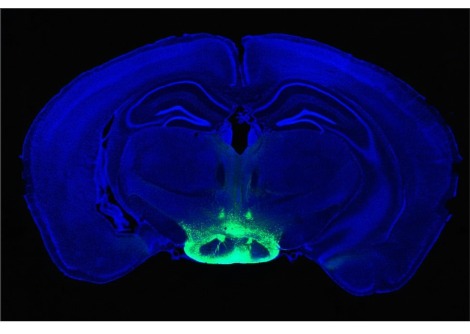

يبدو فقدان الوزن أمراً هيّناً لو استطعت أن تعطّل حاسّة الشمّ لديك أثناء تناولك لطبق شهيّ من اللحم المقدد. نشرت إذاعة سي بي اس نيوز CBS News بأنّ هنالك دراسة جديدة كشفت عن أنّ الفئران الفاقدة لحاسّة الشمّ فقدت الوزن بطريقة أكبر من الفئران التي تتمتّع بالقدرة على شمّ الطعام الذي تتناوله. هذا ما يجعلنا نعتقد بأنّ حاسّة الشمّ القويّة قد تكون السبب وراء إفساد حميتك الغذائيّة.

تبعاً للمعلومات الجديدة، فإنّ الفئران التي تمتلك حاسة الشمّ كانت قد اكتسبت ضعف الوزن الذي اكتسبته الفئران التي تفتقد لحاسّة الشمّ. بالإضافة إلى ذلك، كان هنالك عدد من الفئران التي تمتلك حاسّة شمّ قويّة تمّ مقارنتها مع الفئران الفاقدة لحاسّة الشمّ. اكتسبت الفئران التي تمتلك حاسّة شمّ أقوى من المعتاد وزناً أكبر حتّى من الفئران التي تمتلك حاسّة شمّ عاديّة.

قالت مؤلفة الدراسة سيلين ريرا لإذاعة السي بي اس CBS: "تعدّ هذه الدراسة واحدة من أوائل الدراسات التي تُظهر بأنّه إذا ما قمنا بالتلاعب بالمدخلات الشميّة فسنستطيع عندها تغيير طبيعة استقبال الدماغ لتوازن الطاقة وكيفيّة تنظيمه لهذه الطاقة".

تعتقد ريرا بأنّ النتائج الجديدة تبشّر بمستقبل واعد لعلاجات فقدان الوزن. تقول ريرا للإذاعة: "ما يميّز الأعصاب الشميّة هو أنّها فريدة من نوعها، فهي لا تقع في الدماغ ولكن في الأنف، لذلك، ربّما نستطيع في المستقبل أن نقوم بتعطيلها بطريقة غير جراحيّة، وقد يساعدنا تعطيل هذه الأعصاب لعدّة أشهر على مساعدة الأشخاص على فقدان الوزن".

يقول "أندرو ديلين" مؤلّف الدراسة الأوّل وأستاذ في معهد هوارد هيوز الطبي في ماريلاند بأنّه لو صحّت هذه النتائج على الإنسان فهذا سيفتح المجال على مصراعيه أمام الباحثين لإيجاد بدائل جديدة لمقاييس عالية جدّاً كإجراء جراحات لعلاج البدانة. يقول ديلين للسي بي اس: "قد تساعدنا هذه الدراسة على تعطيل حاسّة الشم عند مجموعة من النّاس لبضعة أشهر، كستة أشهر مثلاً، إلى حين إعادة ضبط عمليّة الأيض في أجسادهم ومن ثمّ نسمح لهذه الأعصاب بالنموّ مرّة أخرى".